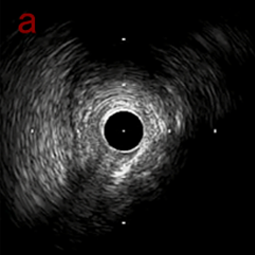

IVUS imaging

IVUSでは8時方向からPD枝がはいいてくる。

PreのIVUSではaの部位のみlipid plaqueを認め削ることでdistal embolismのリスクがあり、そのほかは270度の偏心性石灰化であるがwire biasは良好。

IVUS imaging after low speed 3回

OAS low speedによる引きのsandingを3回行いIVUSを確認するとa-cでは心筋側側へのOASによる良好なbias変化と、それに伴いdの健常側への危険なbias変化を認めた。